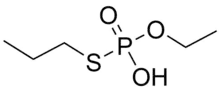

Metabolism

In mammals, metabolism usually proceeds by removal of one or both of the propyl groups and subsequent conjugation. In rats, metabolism is independent of sex, dose, route of administration, or repeated administration, and no parent compound is detectable in faeces or urine. The main metabolite in humans is EPPA, shown below, which can be used as a biomarker for ethoprophos. The dealkylated metabolites have similar toxic effects to the parent compound.[1]